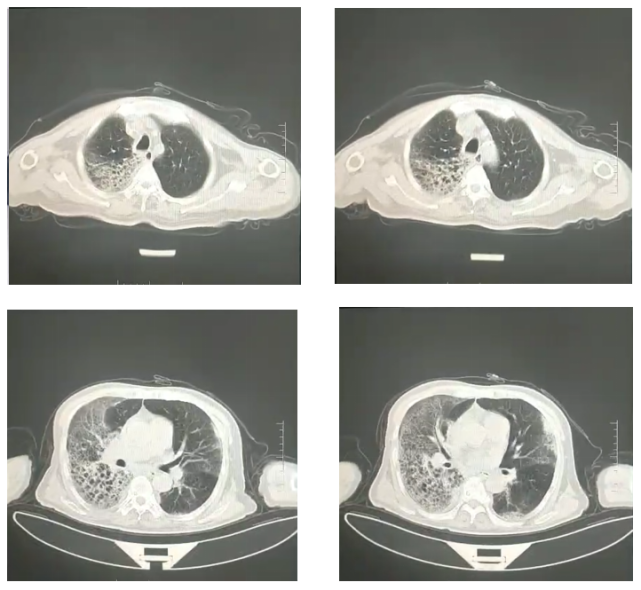

胸部CT:

两肺间质性炎症。两侧少量胸腔积液(图1)。

图1:入院第一天胸部CT,两肺间质性炎症。两侧少量胸腔积液